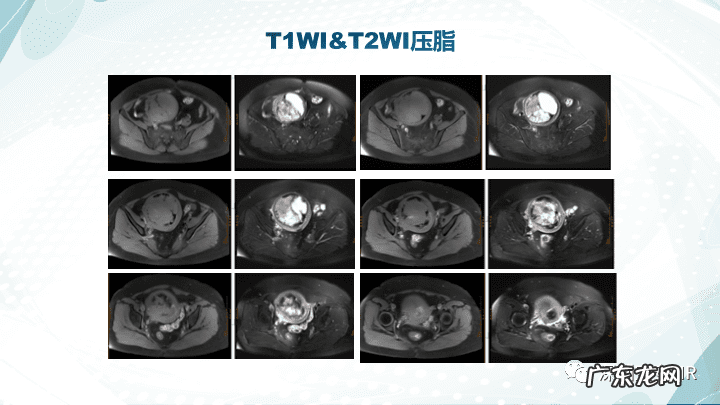

【子宫内膜间质肉瘤病理 子宫内膜间质肉瘤分期标准】下载放射沙龙app,获取更多影像科学习资料,更多学习视频等着你哦